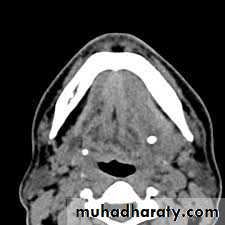

3. Surgical drainage, by using fine needle aspiration guided by CT scan or Ultrasonography.

1. Sialogram: As the neoplasm enlarges it displaces the glandular tissue and its duct system to the periphery producing "grasping fingers" appearance in sialogram.2. CT scan, MRI & USG

2. CT scan & MRI